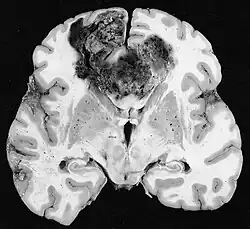

Hersenmetastasen

Hersenmetastasen zijn de meest voorkomende intracraniële neoplasmata bij volwassenen en komen tien keer vaker voor dan primaire hersentumoren. Ze stappen op 20 tot 40 procent van de volwassenen met kanker en worden voornamelijk geassocieerd met long- en borstkanker en melanoom. Deze laesies zijn het gevolg van de verspreiding van kankercellen door de bloedbaan en komen meestal voor op de kruising van grijze en witte stof, waar de dwarsdoorsnede van bloedvaten verandert, waardoor tumorcelembolie wordt opgesloten . 80 procent van de laesies komt voor in de hersenhelften, procent in het cerebellum en 5 procent in de hersenstam. Ongeveer 80 procent van de patiënten heeft een voorgeschiedenis van systemische kanker en 70 procent heeft meerdere hersenmetastasen.

Hersenmetastasen zijn de meest voorkomende intracraniële neoplasmata bij volwassenen en komen tien keer vaker voor dan primaire hersentumoren. Ze stappen op 20 tot 40 procent van de volwassenen met kanker en worden voornamelijk geassocieerd met long-en borstkanker en melanoom. Deze laesies zijn het gevolg van de verspreiding van kankercellen door de bloedbaan en komen meestal voor op de kruising van grijze en witte stof, waar de dwarsdoorsnede van bloedvaten verandert, waardoor tumorcelembolie wordt opgesloten. 80 procent van de laesies komt voor in de hersenhelften, procent in het cerebellum en 5 procent in de hersenstam. Ongeveer 80 procent van de patiënten heeft een voorgeschiedenis van systemische kanker en 70 procent heeft meerdere hersenmetastasen.